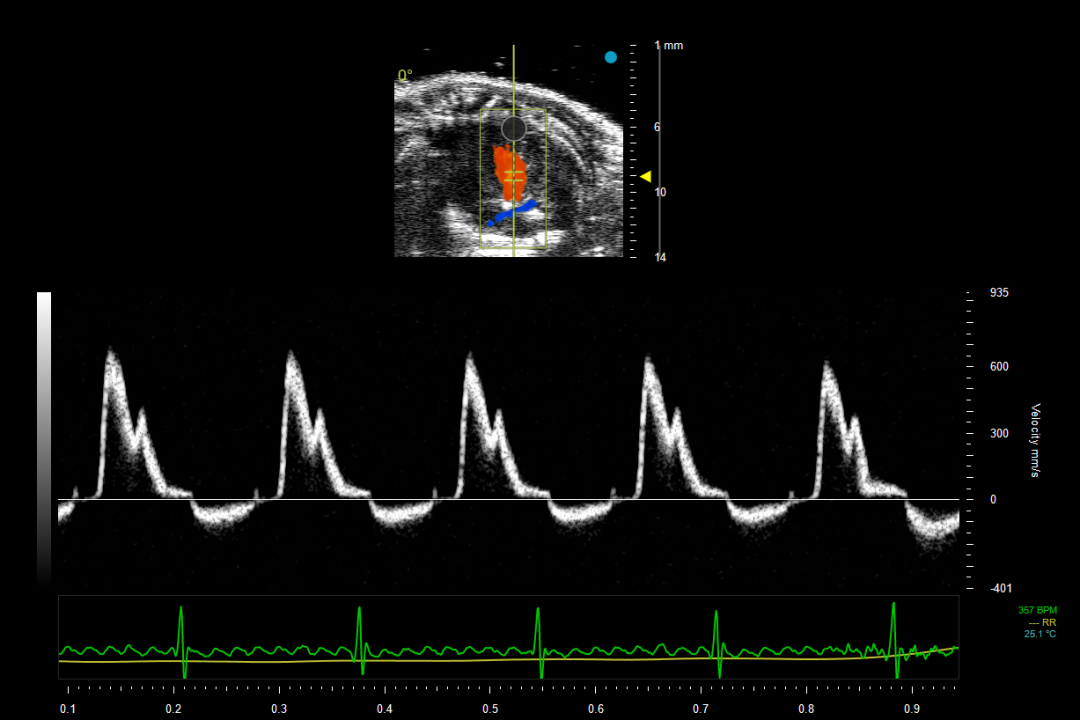

5.此时点击转换彩色多普勒(Color Doppler Flow Imaging,CDFI/CD)模式,取样框放置在左心室、左心房处,可以观察到红色、蓝色分别代表朝向、背离探头的血流,如图4所示,将脉冲波多普勒(Pulsed Wave Doppler, PW)取样容积放在左室血流速度最快的位置,点击转换成脉冲波多普勒模式,注意取样方向与血流方向一致,获取二尖瓣血流动力学信息,如图5所示,可以获取 E 峰、A 峰等定量参数。E 峰代表心室舒张早期被动充盈的血流速度,A 峰代表心房收缩主动充盈的血流速度,比值直接反映舒张期充盈模式。

图5 心尖四腔切面中二尖瓣血流波谱

(Pulsed Wave Doppler)